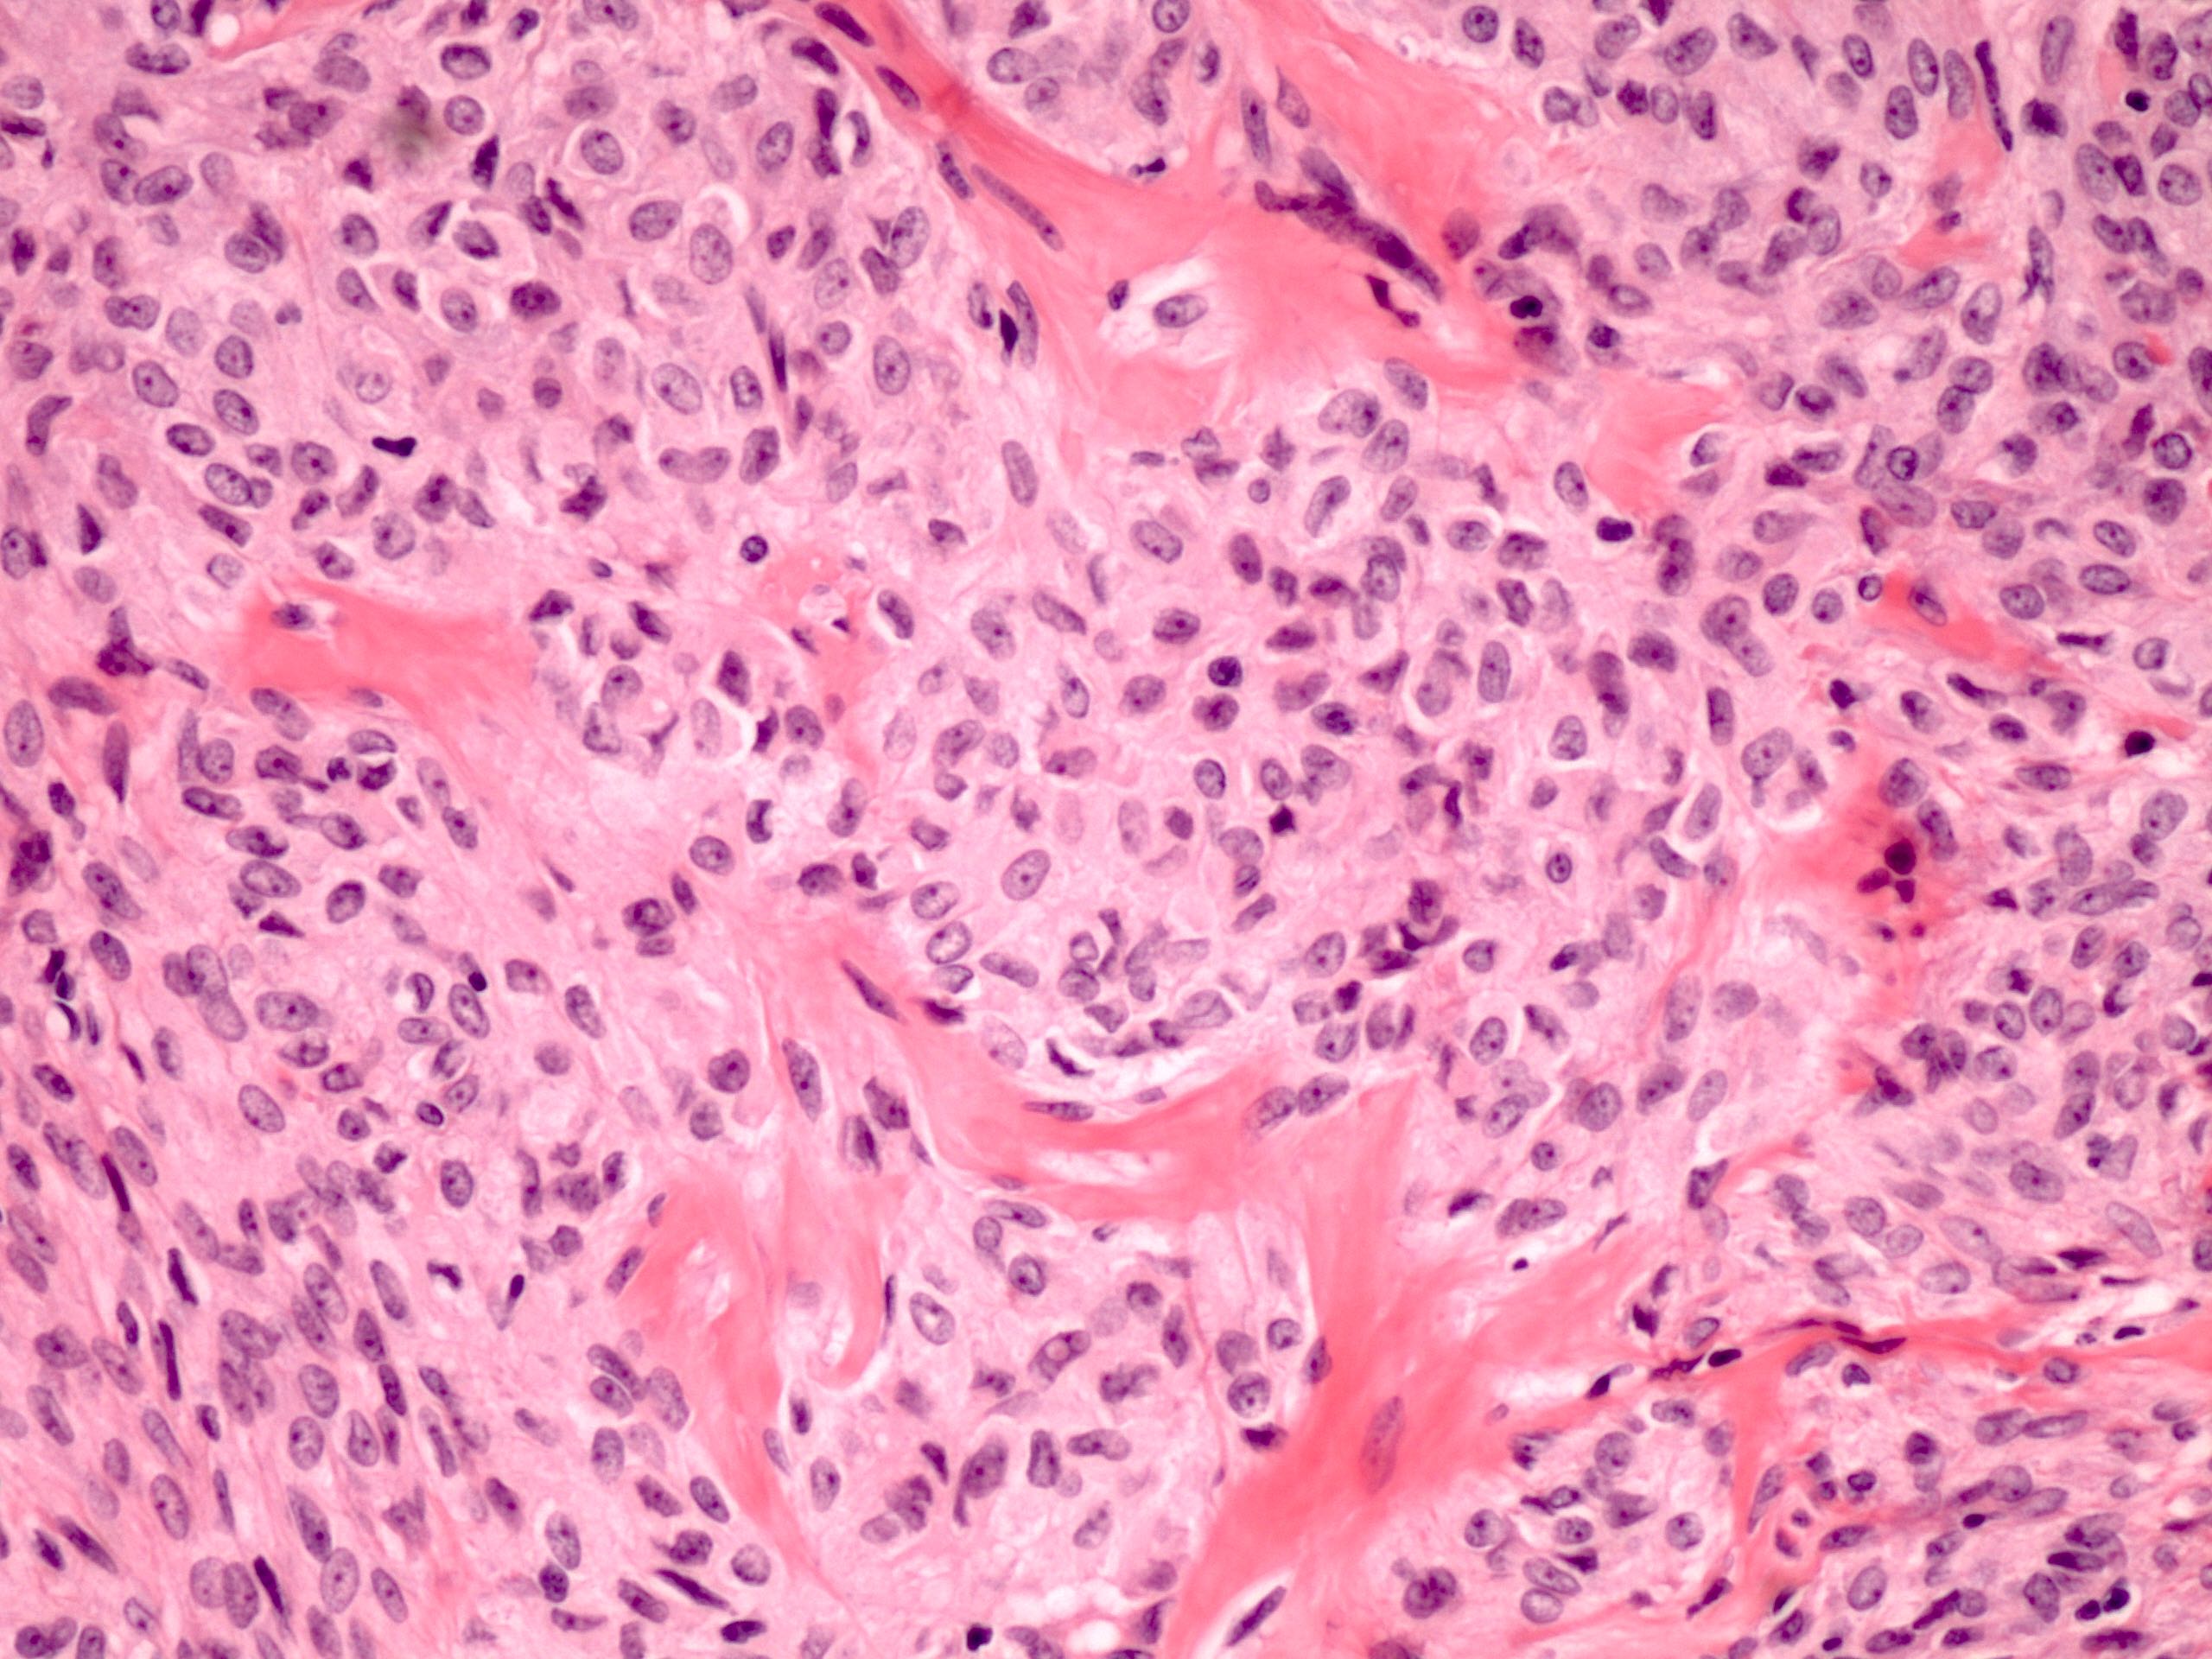

Microscopic (histologic) description

- Predominant population of cells showing ovoid to round nuclei and pale gray cytoplasm, which can be abundant

- Minor component of the tumor may have spindled nuclei, reflecting overlap between fibroma and thecoma

- Indistinct cell membranes impart a syncytial appearance

- Diffuse or nodular growth pattern

- Absent or minimal nuclear atypia

- Mitotic rate usually < 5/10 high power fields

- Hyaline plaques

- Cytoplasmic lipid vacuoles may be present but are not essential

- May show aggregates of cells with brightly eosinophilic cytoplasm (lutein cells)

- Calcification is more common in young patients (Int J Gynecol Pathol 1988;7:343)

- Uncommon features include keloid-like sclerosis, nuclear grooves, bizarre nuclear atypia (Am J Surg Pathol 2014;38:1023)

- Rarely contains a minor component of sex cord elements (Int J Gynecol Pathol 1983;2:227)

- Malignant thecoma: very rare, diagnosis requires diffuse moderate to severe nuclear atypia and high mitotic rate (> 4/10 high power fields) (Am J Surg Pathol 2011;35:e15)

Microscopic (histologic) images

Contributed by Victoria Collins, M.D., Tamara Kalir, M.D., Ph.D., AFIP and @SeoparjooAzmel on Twitter